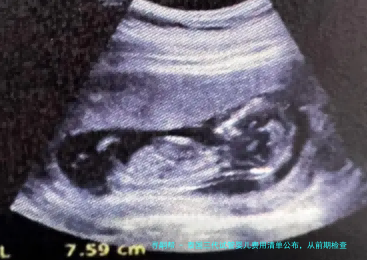

在正规进入试管婴儿周期此前,夫妻两方都需要进行一连串详细的身体检查,以评介生育本领和潜在风险。这些检查是订定个性化医治策略的基础,也是确保治疗安全和成功率的重点。

女性检查项目通常囊括:性激素六个项目(评估卵巢功能)、AMH(抗缪勒管激素,卵巢储备)、阴道B超(检查子宫、卵巢模样)、甲状腺功能、感染病筛查、染色体核型分析等。这一些检查的总花销大约在5000-8000人民币。

取出的卵子与精子在试管受孕后,会形成受精卵,并被培养成胚胎。对于三代试管婴儿而言,胚胎培育到囊胚阶段,然后进行基因学筛选(PGT/PGS/PGD)是必不可少的环节。